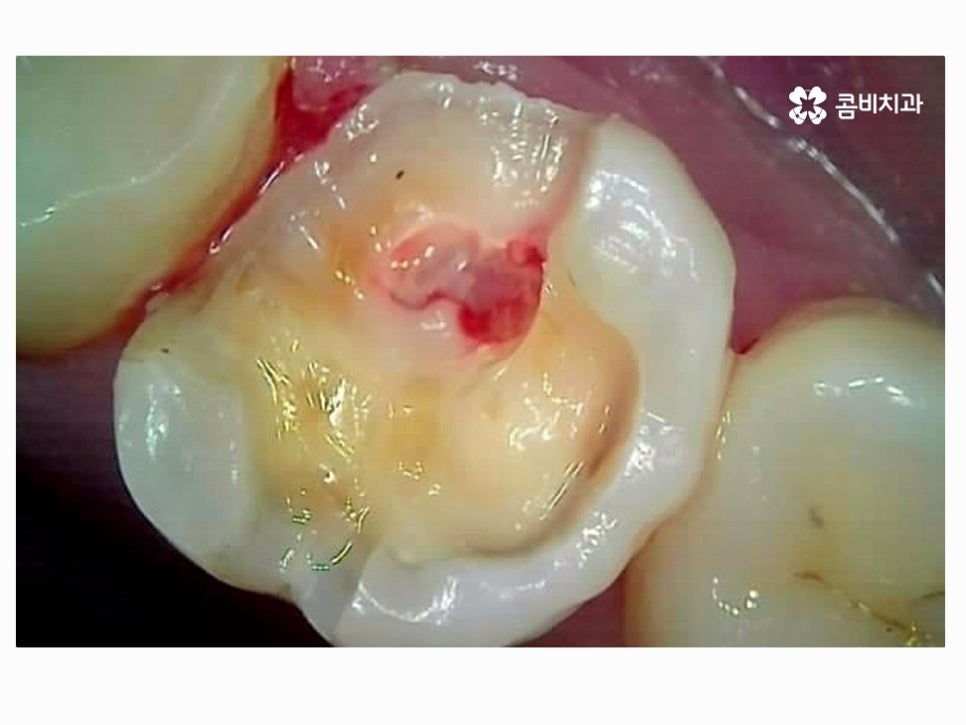

치아는 환자분들이 겉으로만 봐서는 건강한 상태인지 정확하게 알기 어려운데

위 치아 상태만 보더라도 만약 통증이나 이 시림 등을 겪고 있지

않다면 크게 문제가 있다고 느끼지 않을 분들이 많을 거예요.

다시 치아를 자세히 보면 마치 멍이 든 것처럼 살짝 검게 보이기도 하고

이미 환자분께서도 충치로 인한 통증을 호소하고 있는데요.

치아의 인접면 안쪽으로 내부 충치가 이미 깊어진 상황으로